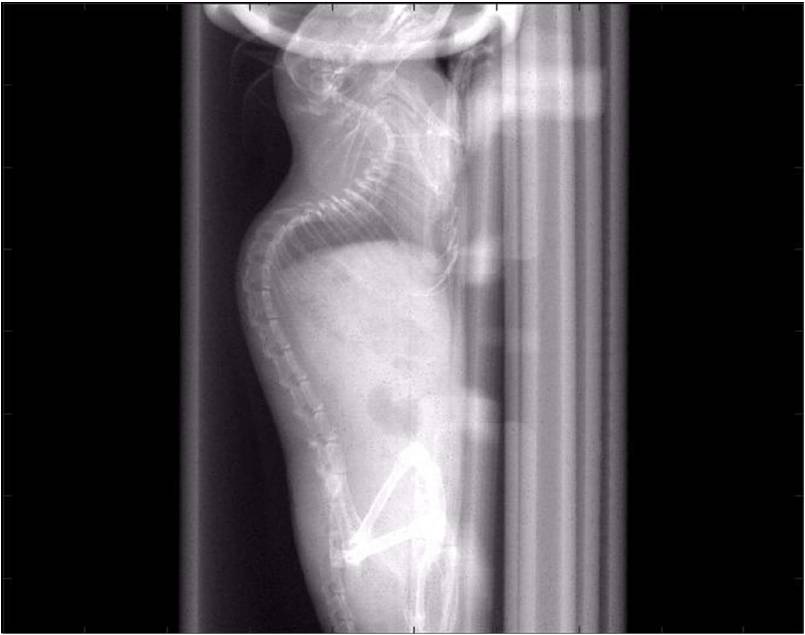

檢測(cè)案例

小鼠股骨

超高分辨率模式下像素大小為9μm。

A軸向和矢狀面顯示小鼠股骨結(jié)構(gòu)。

B用鈦材料植入的穿過骨頭的冠狀切片